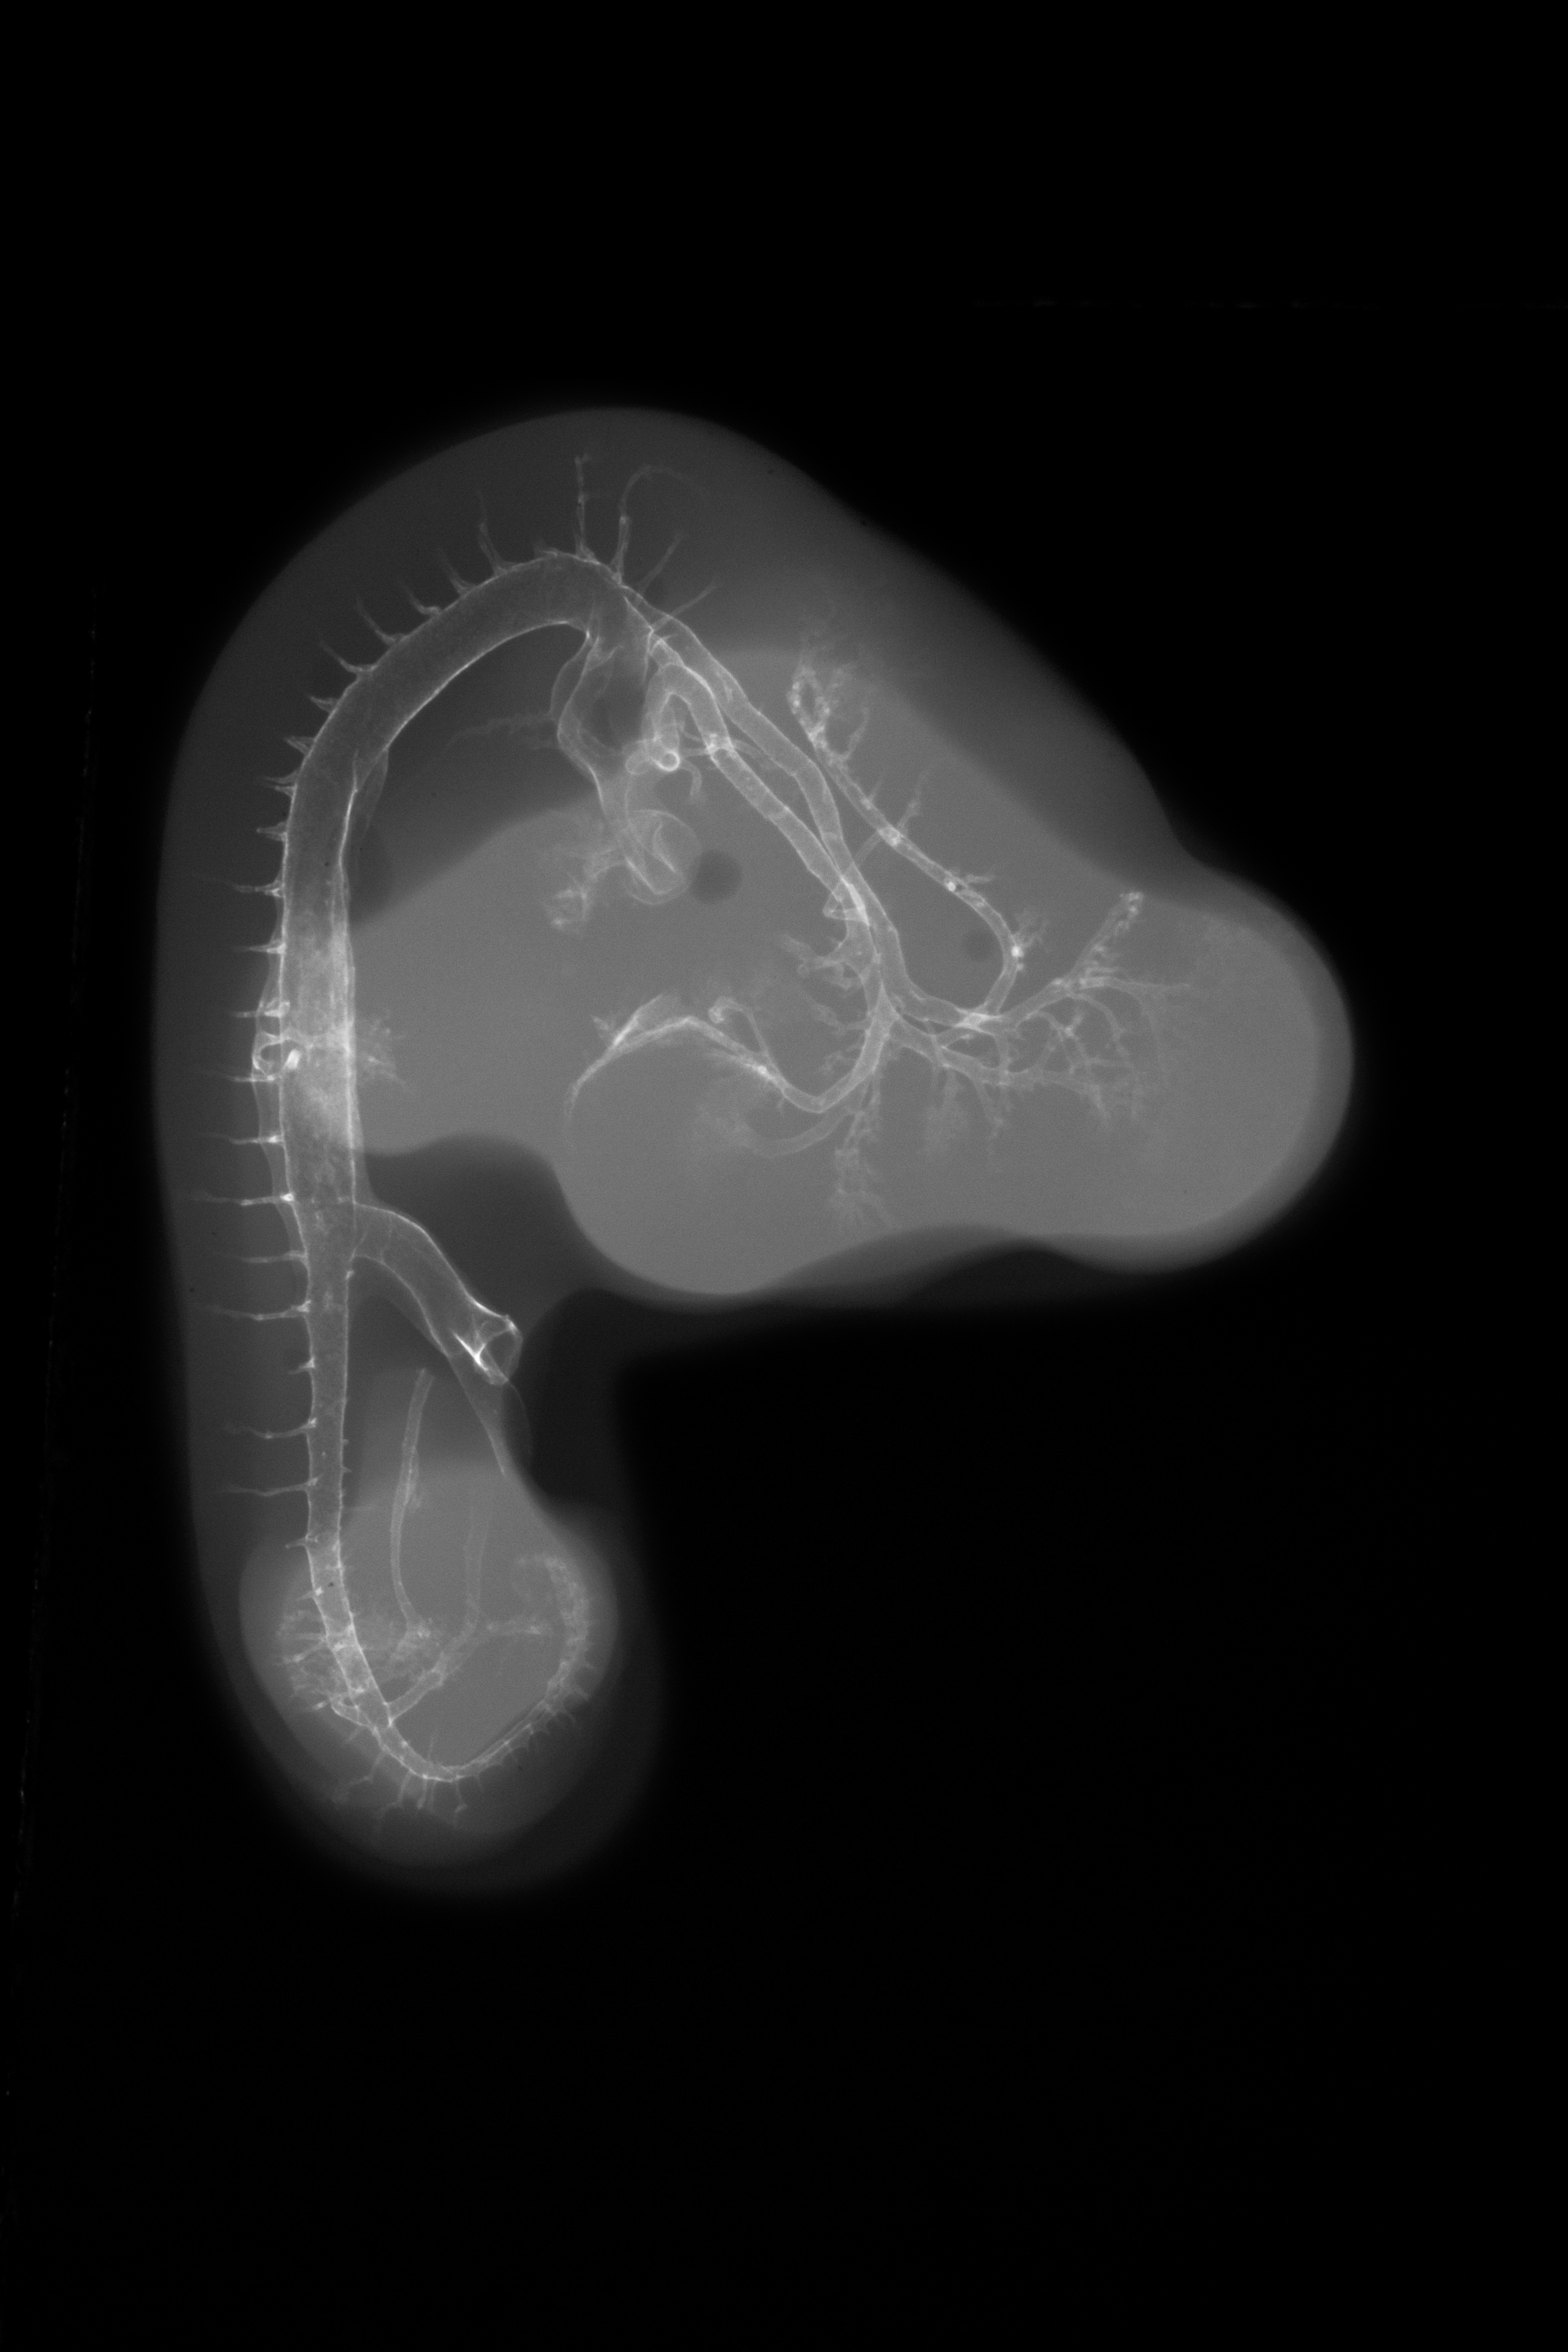

Chick Embryo Microangiography

Hamburger-Hamilton (HH) Stage 24 (approx. 4 - 4.5 days)

X-Ray Micrographs